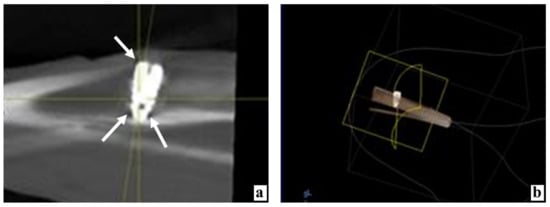

During densitometry and combining the data obtained from all five measurement points around the implanted device, it was found that 3 days after implantation with the use of MSC EVs, the bone density was statistically significantly higher by 47.2% than after the same implantation, but without the application of MSC EVs (Table 1 and Table 2; Figure 1a,b, Figure 2a,b, and Figure 3a).

Figure 1.

Results of studying the bone tissue of the proximal tibial condyle in control rabbits at various times after the introduction of dental implants. (a) X-ray image of the implant in the tibia 3 days after surgery, arrows indicate areas of reduced bone density. (b) Computer 3D modeling of the implant position in the bone on the 3rd day after surgery. (c) On the 3rd day after implantation, there are extensive hemorrhages and a large volume of split bone fragments in the cancellous bone, staining with hematoxylin and eosin. (d) Hemorrhages, vascular distention, and congestion (arrows) near and among the split bone particles 3 days after implant placement, stained with hematoxylin and eosin. (e) On the 10th day, the implant mostly borders with the bone tissue and only in small areas it is adjoined by loose fibrous connective tissue (arrows) with a significant number of hyperemic wide thin-walled vessels, stained with hematoxylin and eosin. (f) After 10 days the implant is delimited from the bone throughout its entire length by connective tissue with wide hyperemic vessels, stained with hematoxylin and eosin.

Figure 2.

The state of the animal tibia at various times after the introduction of dental implants into the proximal condyle with the preliminary injection of MSC EVs. (a) By the 3rd day after the operation, according to the X-ray examination, the tissue rarefaction near the implant neck is insignificant (arrow), in the apex area—only along its sides (arrows). (b) Computer 3D modeling of the device position in the bone 3 days after implantation. (c) Three days after the operation, the fragments of bone detritus adhere tightly to each other, between them there are practically no corpuscles and blood vessels, stained with hematoxylin and eosin. (d) On the 7th day after implantation, next to the split parts of the bone tissue infiltrated by large cells, there are structures of new bone, possibly formed from these bone fragments, stained with hematoxylin and eosin. (e) By the 10th day, only for a short distance, the implant borders with the connective tissue (arrows), stained with hematoxylin and eosin. (f) Partial lysis, consolidation with each other, and ingrowth of split bone fragments into new forming bone structures 10 days after surgery, stained with hematoxylin and eosin.